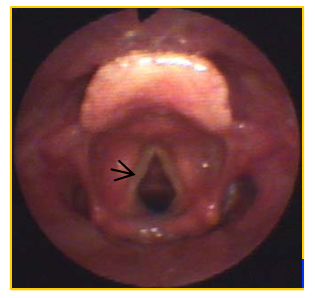

箭头所指为喉癌病变部位

通常在耳鼻咽喉科门诊行电子喉镜检查可发现病变。电子喉镜能深入喉部,清晰地呈现病变部位的形态、大小和位置,如果需要明确病变性质则需行手术切除部分病变组织进行病理检查,这是确诊喉癌的“金标准”。同时需要进一步行喉部的CT或MRI扫描,目的是为了解喉癌的大小和准确位置及范围。如果有条件还可以行PET-CT 检查,它可以从代谢层面评估肿瘤的活性,发现潜在的转移病灶,对肿瘤的分期和预后判断具有重要价值。结合喉部肿瘤大小,颈部淋巴结转移情况及全身转移情况进行分期,越早治疗,治疗效果越好。晚期效果较差而且保留喉的可能性很小。